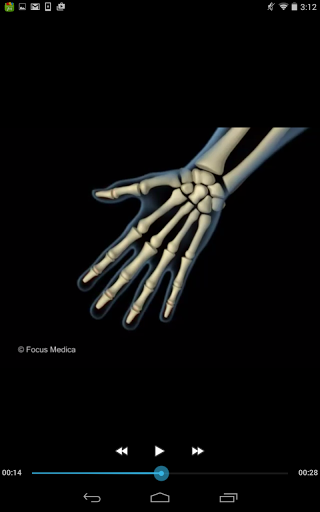

The FOCUS Animated Pocket Dictionary of RHEUMATOLOGY is the first ever animated dictionary in the subject. A valuable reference for physicians and students alike, it covers 100 rheumatology related terms and definitions. All the definitions have been graphically described with the help of 3D animations and are accompanied by text definitions.

The Focus Animated Pocket Dictionaries are the world’s first ever animated dictionaries that provide definitions of medical terms with the aid of realistic and narrated 3D animations, complimented with text definitions. Terms arranged alphabetically making definitions easy to search. These unique visual dictionaries are excellent reference sources for health professionals, students and health consumers. The videos play independent of the internet once downloaded.